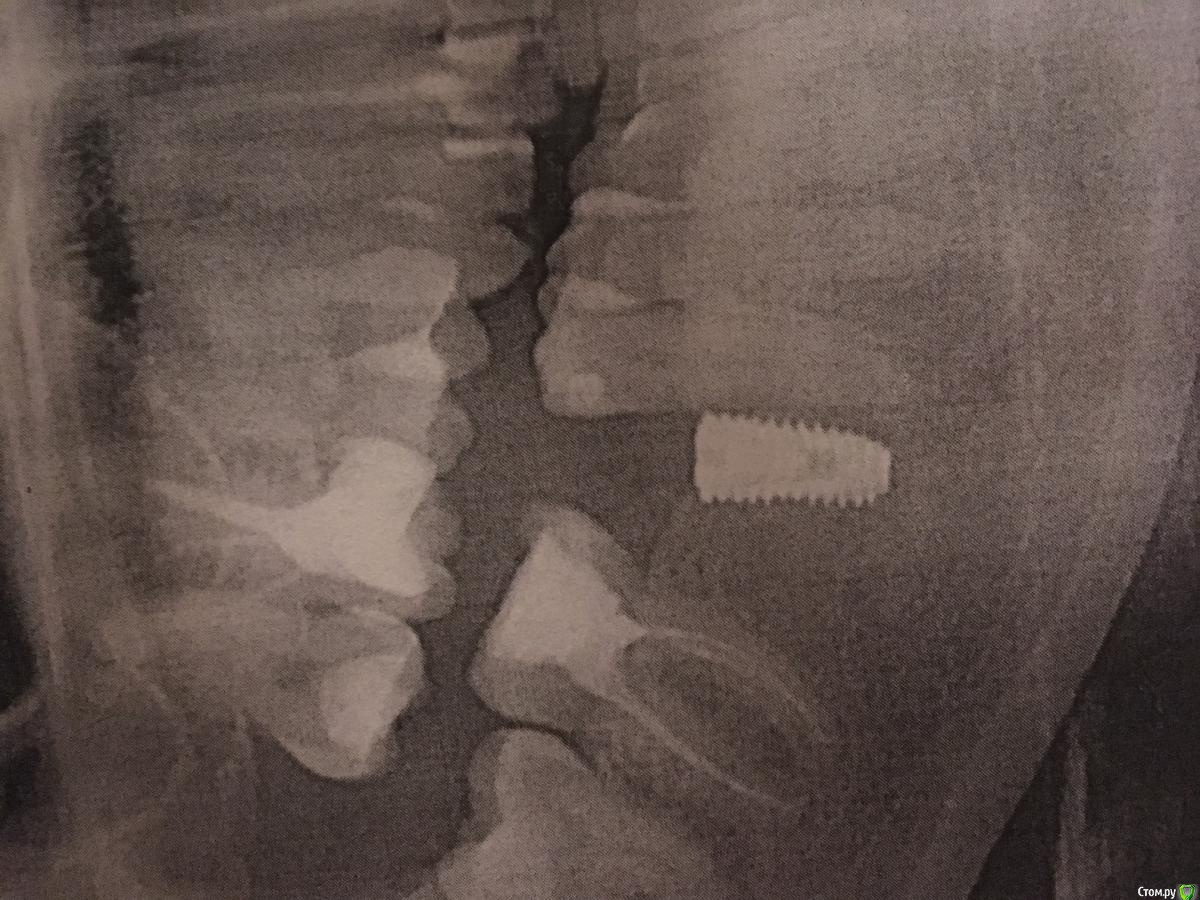

evaverkina Опубликовано 21 февраля, 2018 Поделиться Опубликовано 21 февраля, 2018 (изменено) Добрый вечер всем. Установили 3 импланта 10 февраля 2018г. Сегодня сделала панорамный снимок, имплант очень близко к зубу 45, зуб начал побаливать. Болит при постукивании. Доктор утверждает что все хорошо. Допустимо ли такое расположение импланта к зубу? Есть ли вероятность что имплант затронул зуб? Изменено 21 февраля, 2018 пользователем evaverkina Ссылка на комментарий